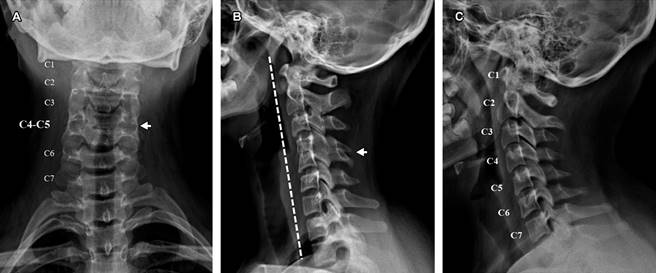

Se trata de paciente femenino de 14 años, que acudió a la consulta con síntomas de dolor cervical unilateral intermitente, cefalea relacionada con la flexión/extensión del cuello y ocasional mareo, sin antecedentes de traumatismos. En la exploración, se observó un cuello corto, dolor en la palpación de la musculatura cervical y limitación en la hiperextensión y rotación cervical. La radiografía simple de columna cervical reveló sinostosis en C4-C5, rectificación de la lordosis cervical y limitación en los rangos de movilidad (Figura 1). Se inició tratamiento analgésico y miorrelajantes, con mejoría clínica.